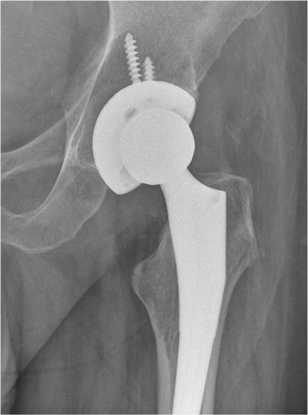

Перед оперативным лечением по назначению клинического фармаколога проведен курс комбинированной антибактериальной терапии: меропенем 2000 мг 3 раза в сут. в/в, амикацин 1000 мг 1 раз в сут. в/в в течение 15 дней. 27.03.2023 проведена резекция головки левой бедренной кости, установка артикулирующего двухслойного спейсера с гентамицином (4 г) (рис. 2). ПЦР операционного материала от 28.03.2023: ДНК микробактерии туберкулеза (МБТ) не обнаружена. Послеоперационный период протекал без осложнений.

Рис. 2. Рентгенограмма левого тазобедренного сустава пациента Ш. в первые сутки после операции по установке артикулирующего цементного спейсера с двухслойной головкой. Наружная цементная мантия содержит 4 г гентамицина